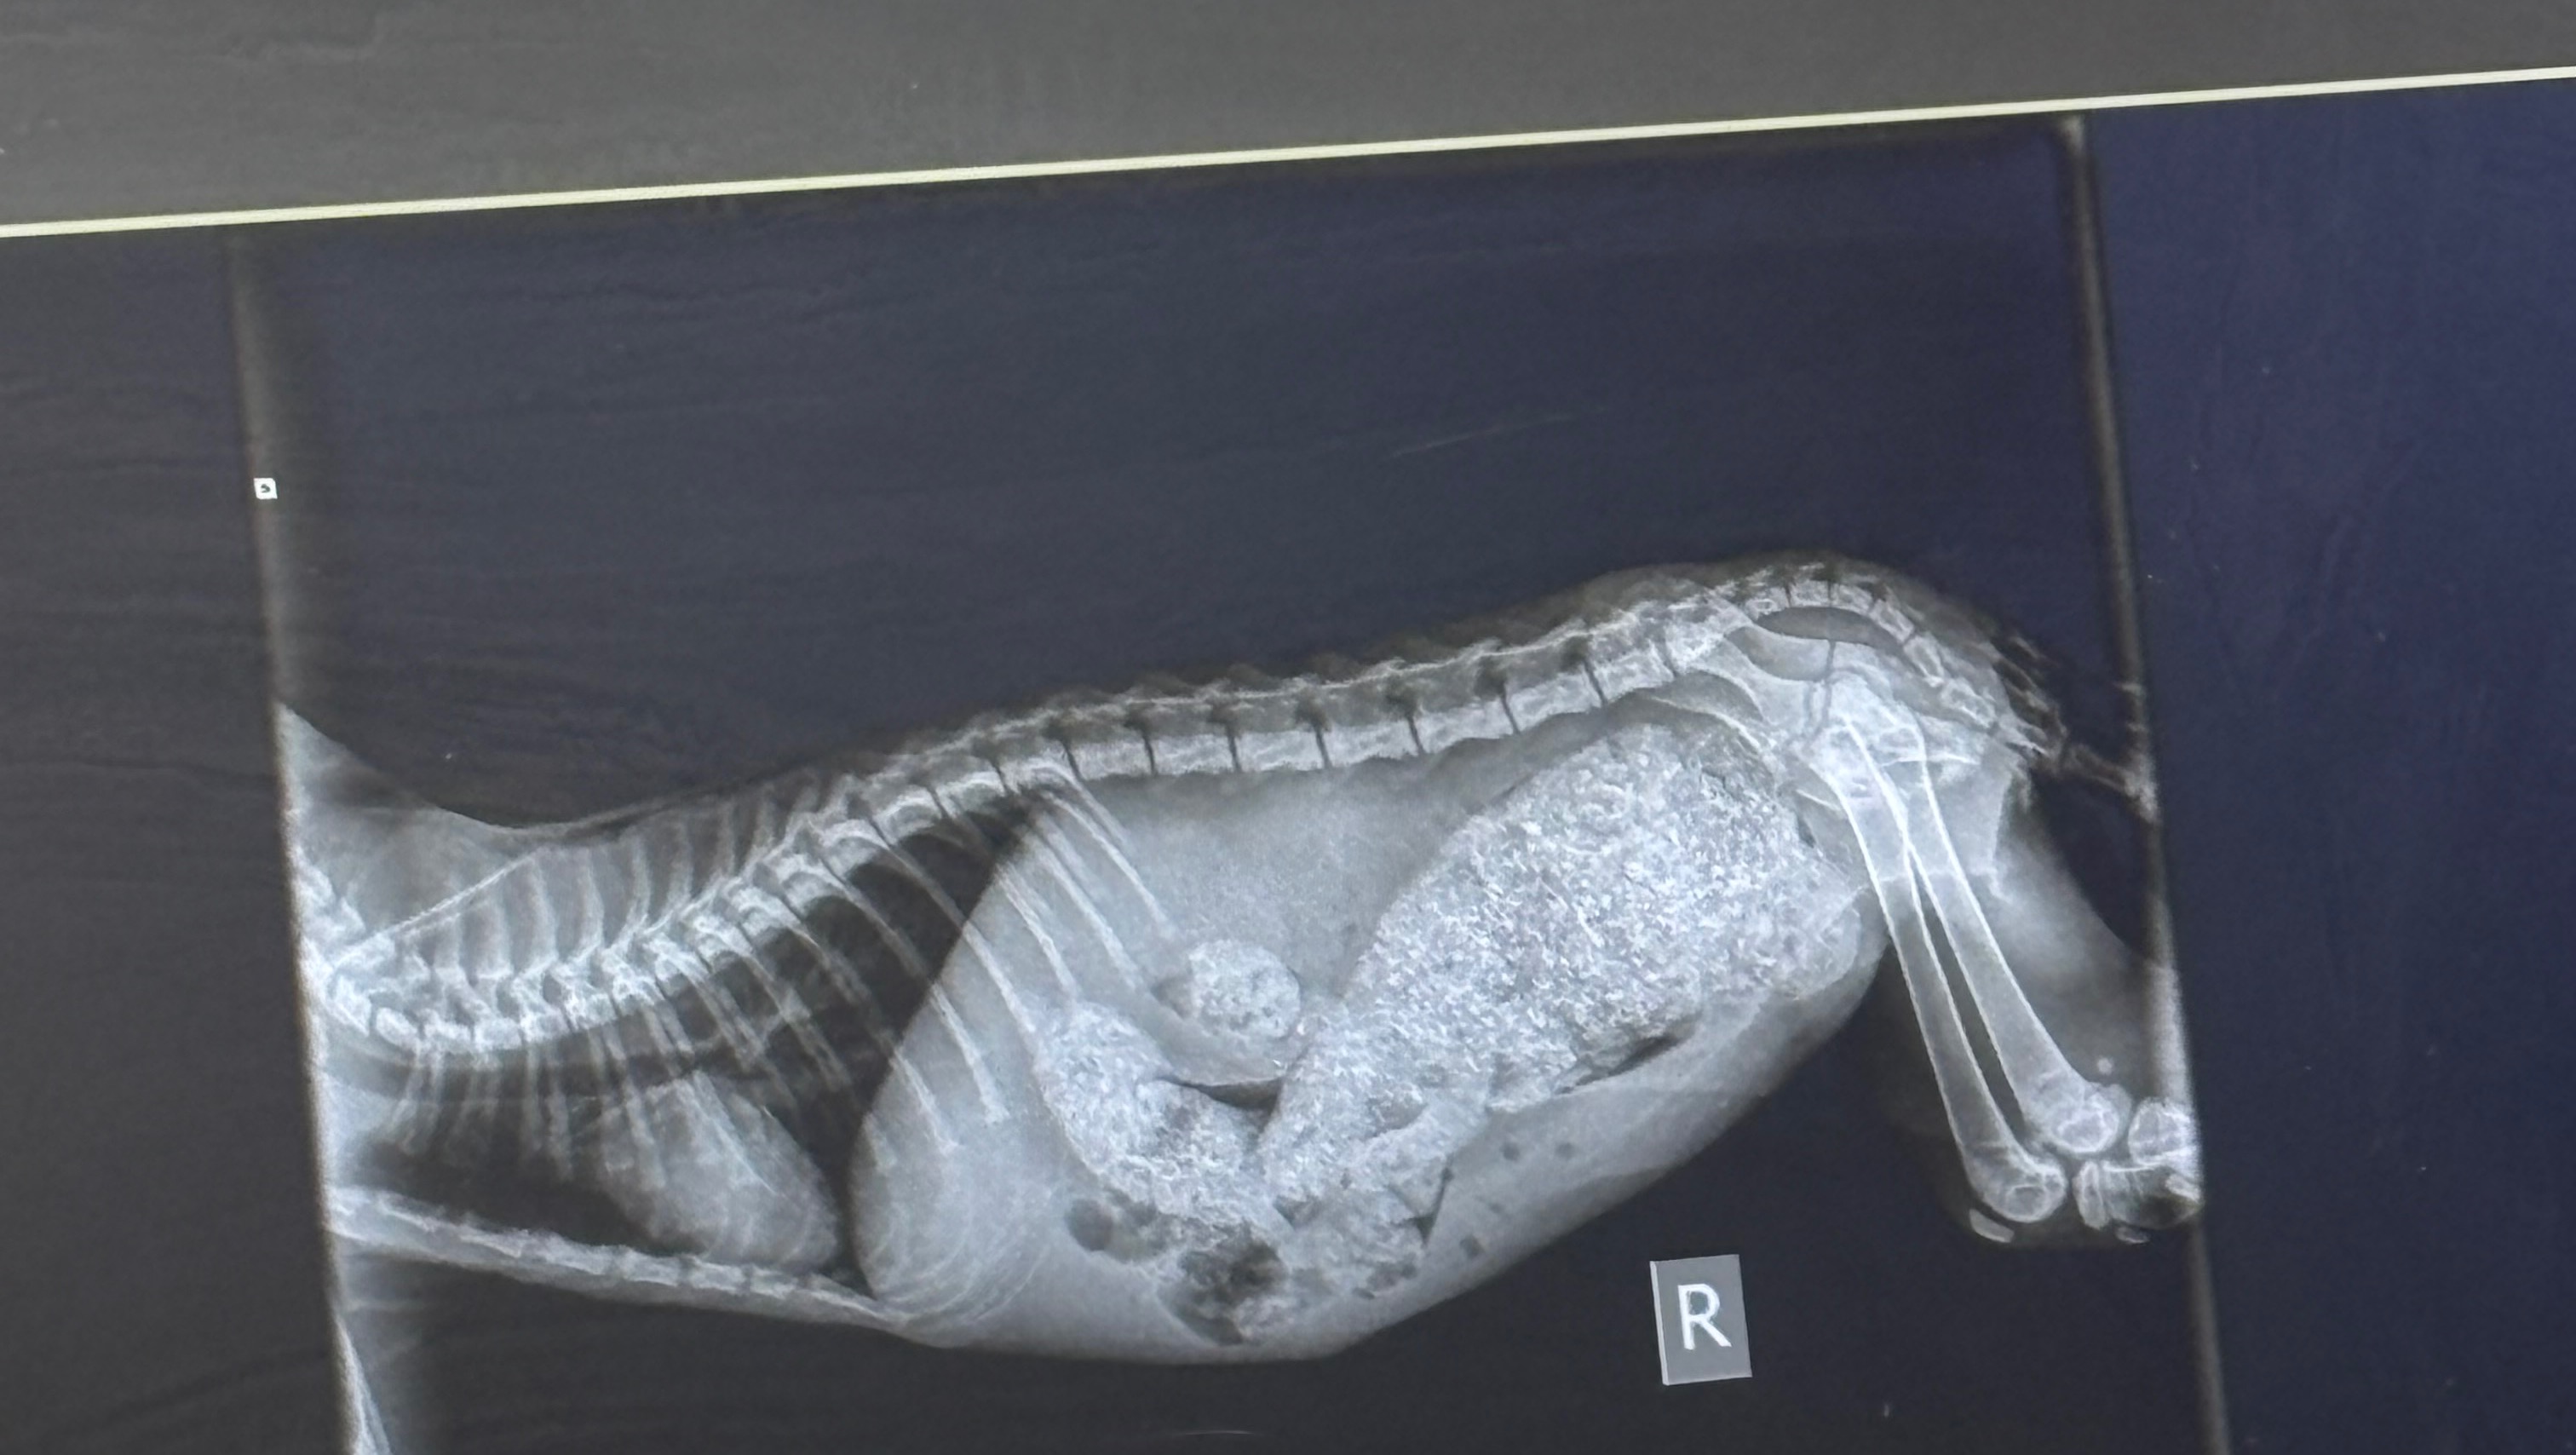

And that’s exactly what happened to Pecan! Her X-rays showed her filled with the most hardened poop the vets had seen in a kitten, and she is now hospitalized while the vets attempt to break up the mass of poop. Unfortunately, her prognosis is guarded, and she may need to have surgery to remove the poop if they can’t get it to pass with enemas, medication, and sedated massage.